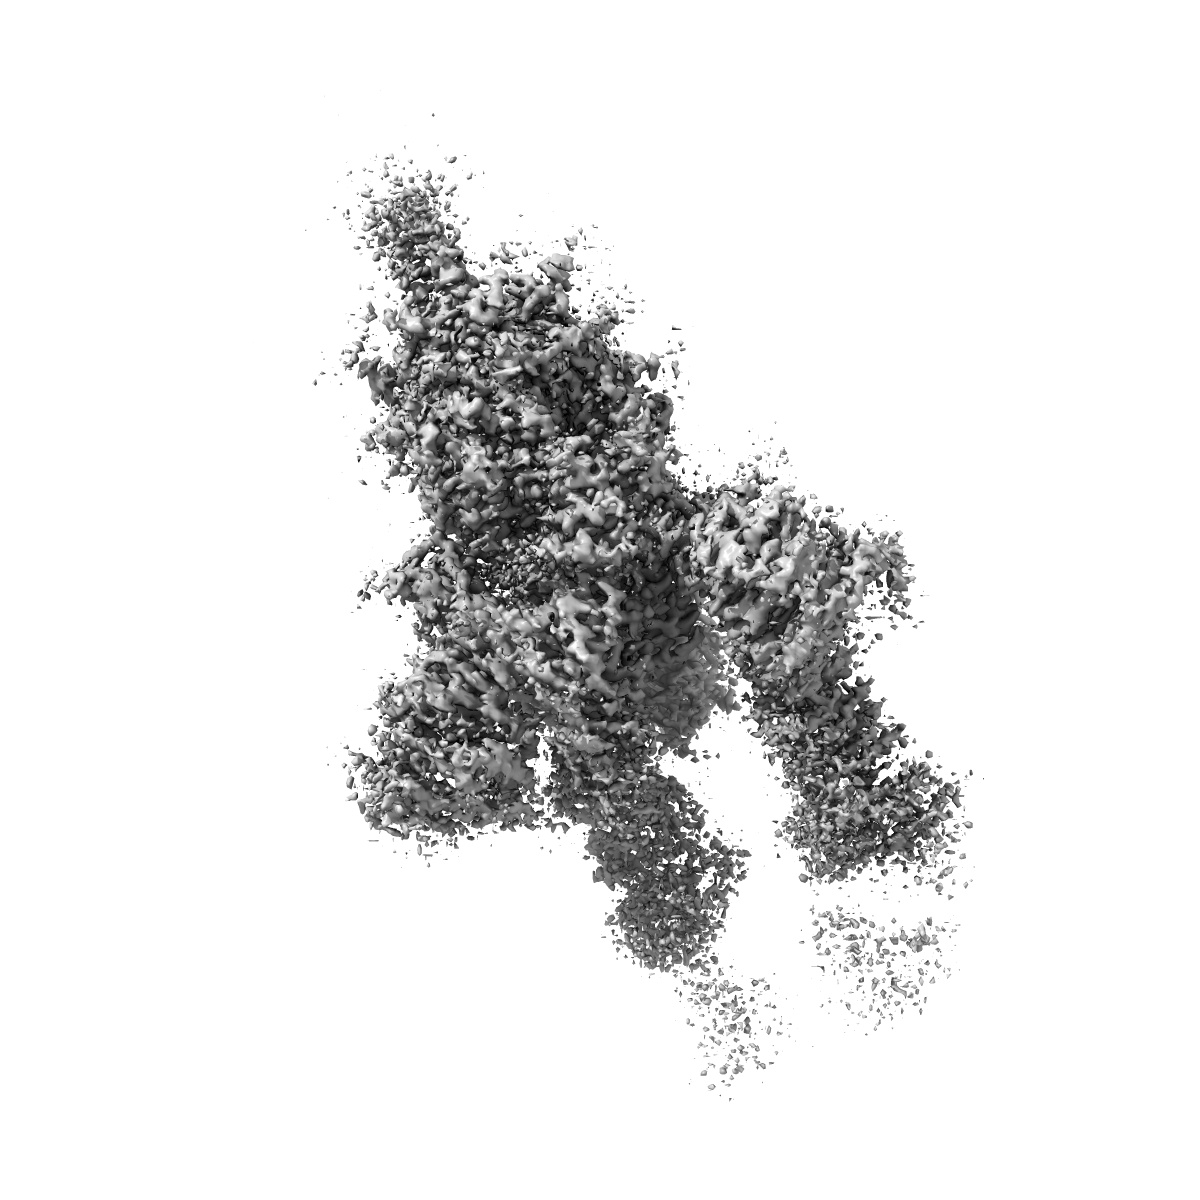

S protein of SARS-CoV-2 in complex bound with P5A-2G9

Single-particle2.7 Å

Sample: S protein of SARS-CoV-2 in complex bound with P2B-2G9

Fitted models: 7czt

Structural basis for bivalent binding and inhibition of SARS-CoV-2 infection by human potent neutralizing antibodies.

(2021) Cell Res , 31 , 517 - 525